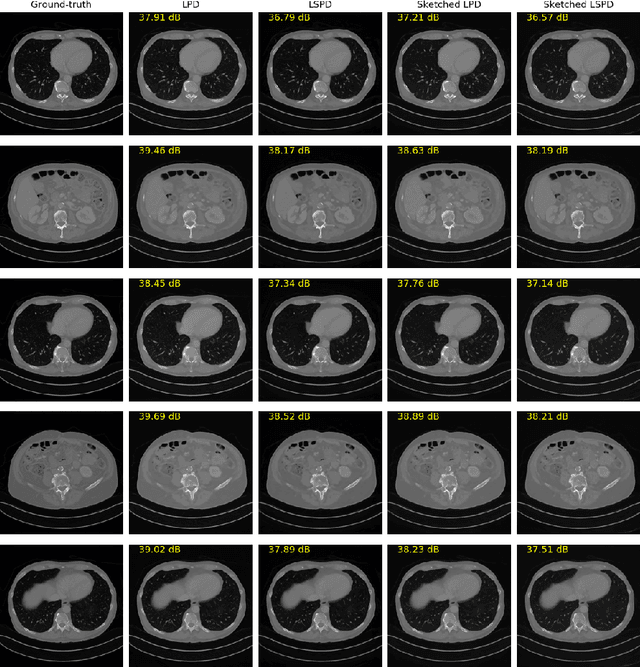

In this work we propose a new paradigm for designing efficient deep unrolling networks using operator sketching. The deep unrolling networks are currently the state-of-the-art solutions for imaging inverse problems. However, for high-dimensional imaging tasks, especially the 3D cone-beam X-ray CT and 4D MRI imaging, the deep unrolling schemes typically become inefficient both in terms of memory and computation, due to the need of computing multiple times the high-dimensional forward and adjoint operators. Recently researchers have found that such limitations can be partially addressed by stochastic unrolling with subsets of operators, inspired by the success of stochastic first-order optimization. In this work, we propose a further acceleration upon stochastic unrolling, using sketching techniques to approximate products in the high-dimensional image space. The operator sketching can be jointly applied with stochastic unrolling for the best acceleration and compression performance. Our numerical experiments on X-ray CT image reconstruction demonstrate the remarkable effectiveness of our sketched unrolling schemes.